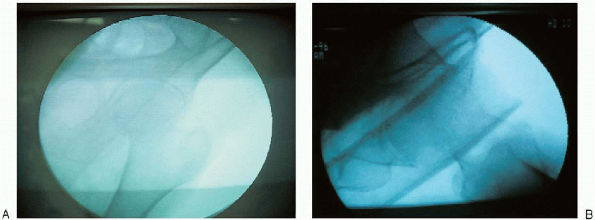

![]() |

FIGURE 21-15. AP (A) and lateral (B)

radiographic confirmation that nonobstructive biplanar radiographic visualization of the entire proximal femur, including the hip joint, is obtainable. |

ensure that the fracture has remained reduced and that nonobstructive

biplanar radiographic visualization of the entire proximal femur,

including the hip joint, is obtainable (Fig. 21-15).